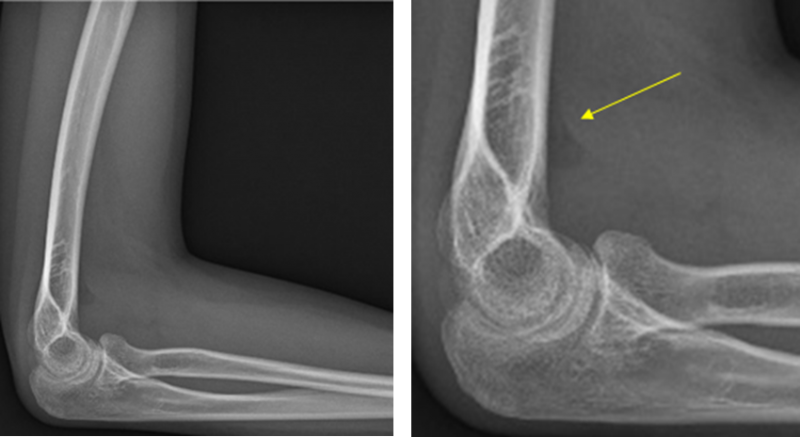

그러면서 실제 방사선 장치로 촬영한 결과를 예로 제시했다.

이들은 “X-ray에서 보이는 뼈에는 골절소견이 보이지 않지만 오른쪽 영상의 화살표가 가리키는 검은 부분은 골절에 의해 관절에 물에 차서 지방을 들어올려 발생한 것”이라고 설명했다.

그러면서 “X-ray 판독은 뼈뿐만 아니라 연조직에서 보이는 이런 소견을 확인할 줄 아는 능력이 필요하며, 이상이 있다면 원인을 명확히 알기 위해 추가검사 여부를 결정해야 한다”며 “만약 이 X-ray를 찍고도 정상으로 판독하여 추가검사를 시행하지 않았다면 잘못된 진단을 내린 것”이라고 강조했다.